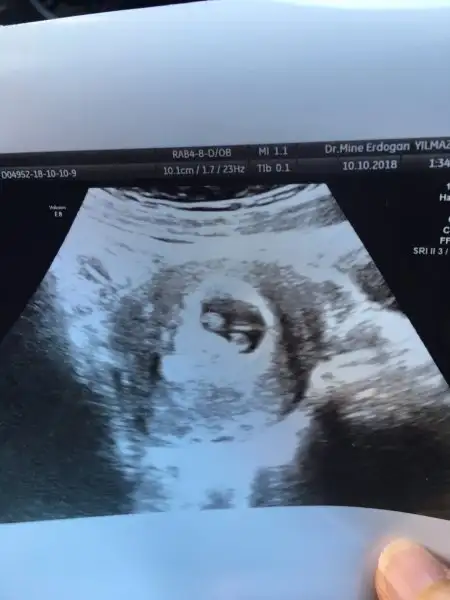

Kızlar dün akşam aniden ağrısız kanamam oldu hemen acile gittik bakıldı çok bir sorun yok dendi yatcaksin tuvalet harici kalkma dedi doktor iğne yaptı ve 200mg progestan başladı bugün kendi doktoruna gittim kanamam bir miktar devam ediyor ultrasonda doktor iki kese birden gordu biri biraz daha küçük ikiz gebelik büyük ihtimal dedi tabi ben soookhayirlisi bakalım hiç kalkmak yok dedi nasıl olacaksa

Canım ilk gittiğimde keseyi net görememişti haftaya gidecektim aslında net şekilde kese ve kalp atışlarını duyarız demişti..ama ani kanama olunca bugün baktı ve 2 kese var dedi